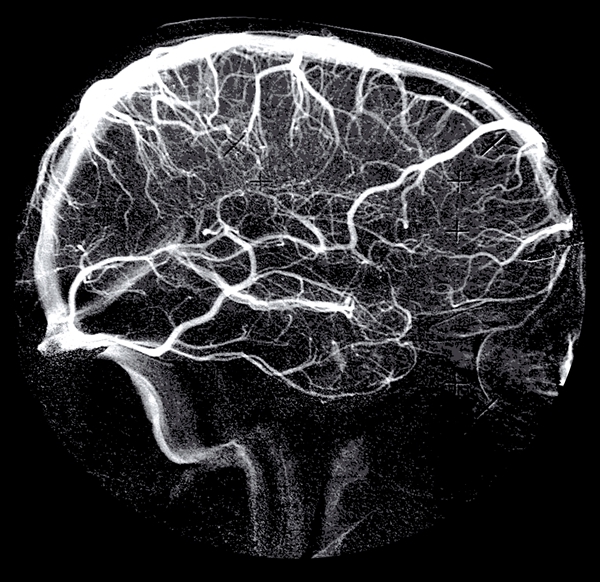

- церебральная ангиография;

- магнитно-резонансное исследование (МР ангиография);

Методы обследования

Здесь спектр очень широкий. В зависимости от предполагаемой причины головной боли пациент может быть направлен на магнитно-резонансную томографию с контрастом или в сосудистом режиме, на ангиографию, на биопсию артерии, на люмбальную пункцию, на УЗИ сосудов. В большинстве случаев, если не списывать всё на «сосуды», а отнестись к решению проблемы со всей тщательностью, реальную причину удается установить.